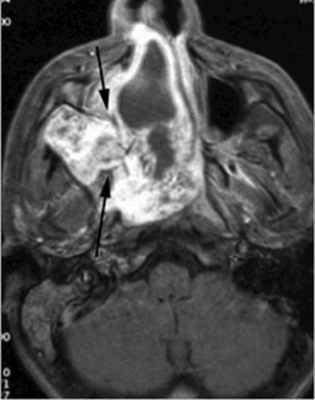

Ангиофиброма

Доброкачественное сосудистое объемное образование с медленно агрессивным ростом; локализуется в полости носа; растет вокруг задней стенки полости носа, по краям крыловидно-нёбного отверстия; на ранних стадиях пенетрирует в крыловидно-нёбную ямку (стрелки), прорастает медиальную крыловидную пластинку